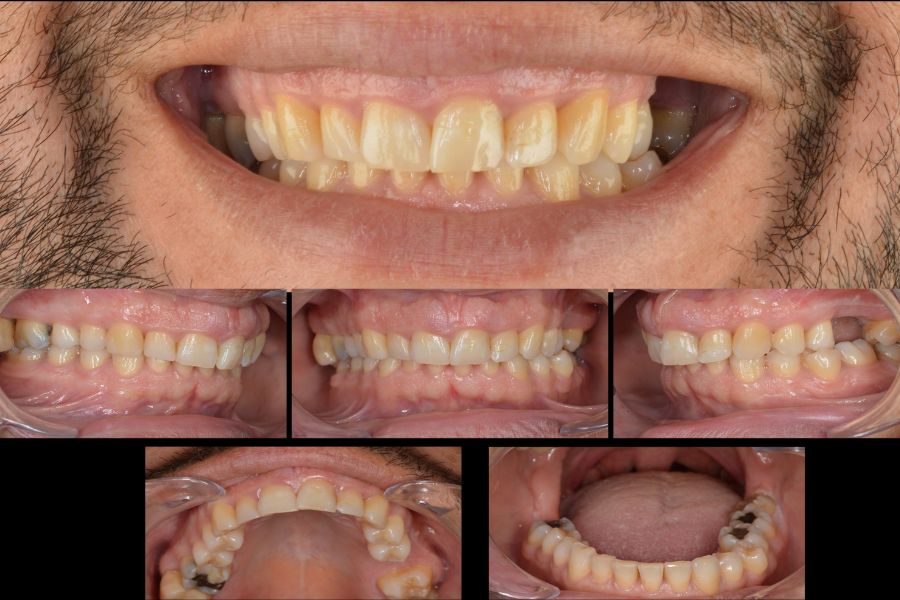

Estado inicial de la boca del paciente

El paciente acudió a Clínicas Den por un motivo principalmente estético. No se sentía a gusto con el tamaño de sus dientes y que su sonrisa no era del todo armónica.

En la exploración clínica detectamos varios factores clave. Presentaba sonrisa gingival, ausencia de un molar superior y una oclusión que no ofrecía estabilidad funcional.

Las primeras imágenes reflejan el estado inicial de su boca desde distintos ángulos, donde ya se aprecia la desproporción dental y la falta de soporte posterior causada por la muela ausente.